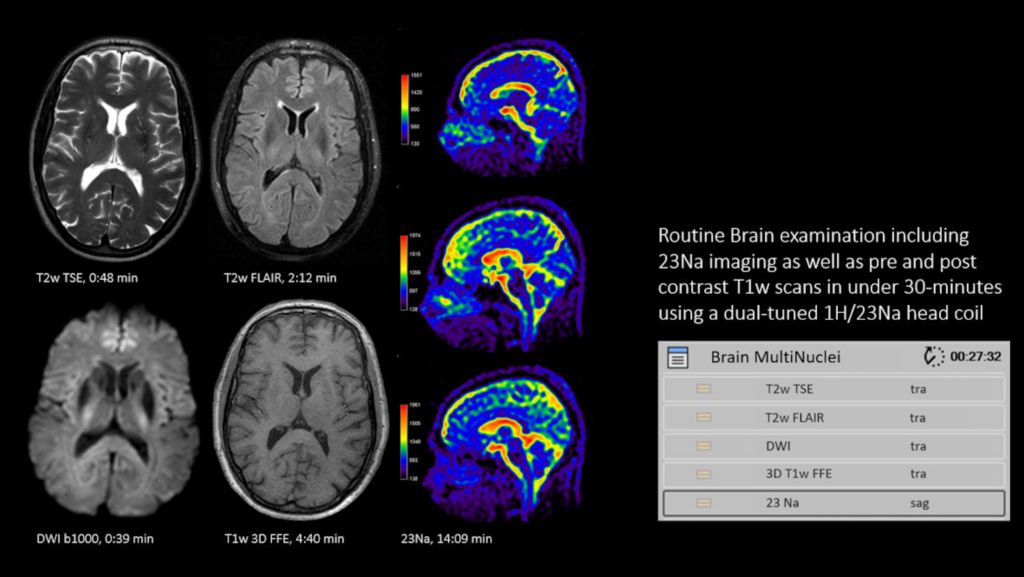

In addition to a seamless user interface, the dual tuned head coils from <b><i><i>RAPID biomedical</i></i></b> enable brain exams, including acquisition of proton and other nuclei, without switching coils. This allows you to schedule your multi-nuclei studies as part of your clinical exam time slots. A full brain study, including both proton (1H) and sodium (23Na) imaging can be completed in 30 minutes¹, all organized in one ExamCard using the same dual tuned head coil. A sodium (23Na) brain exam can be completed in less than 15 minutes².

The dual tuned head coil from RAPID Biomedical allow you to perform brain exams, including acquisition of proton and other nuclei (31P, 13C, 23Na), without switching coils, in routine scan times. A full brain study, including both proton (1H) and sodium (23Na) imaging can be completed in 30 minutes, all organized in one ExamCard, using the same dual tuned head coil. A Sodium (23Na) brain scan can be completed in less than 15 minutes. Workflow does not differ from proton imaging. Multi-nuclei imaging and spectroscopy can be run and reconstructed directly from the standard user interface. The ExamCard interface immediately recognizes the dual tuned head coil. And the nucleus is just a scan parameter like any other sequence parameter. Viewing of multi-nuclei images and spectra, as well as sending data to PACS, is fully integrated. Combined with our multi-nuclei specialist package, the dual tuned head coil allows to explore new imaging pathways by integrating multi-nuclei studies in your day-to-day workflow.

1 Measured from start of first scan to end of last reconstruction. Includes 1H (T2w TSE, T2w FLAIR, SSh DWI, and 3D T1w FFE pre&post) + 23Na (with a voxel size of 4mm isotropic).

2 For 4 mm isotropic voxels